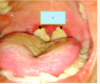

What is labelled A Chlamdyia infection Endometriosis Fibroids Gonorrhea infection Polycysitc ovary syndrome